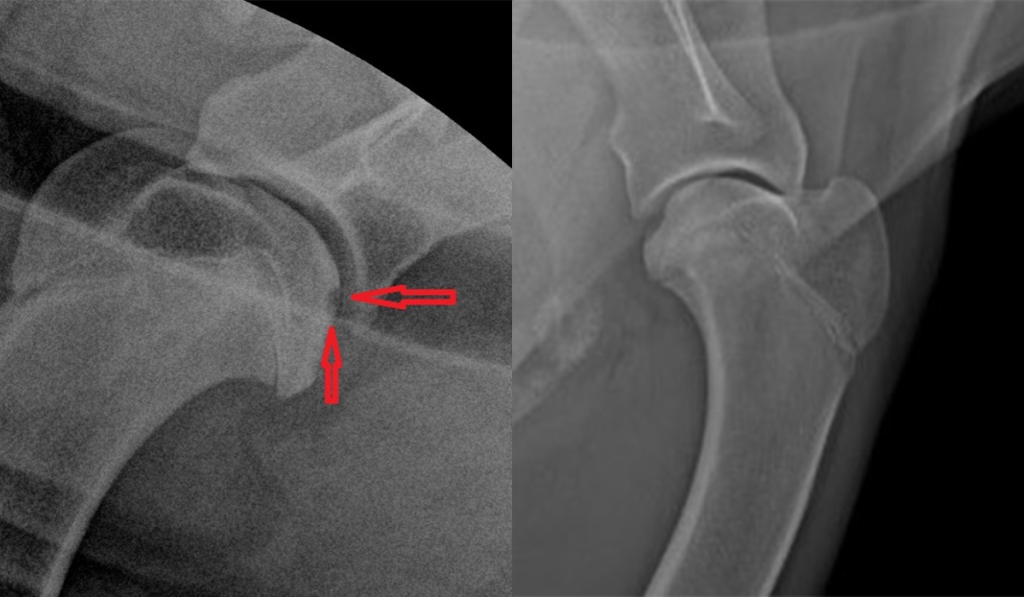

Диагностика расслаивающего остеохондрита у собак заключается в проведении рентгенологического исследования (в нескольких проекциях). В некоторых случаях рекомендуется проведение артроскопии. При помощи этого метода можно точно поставить диагноз, дать оценку состоянию сустава и даже провести хирургическое лечение патологии.

При проявлении РОХ отмечается прободение (ямка) по месту отслоения хряща, что приводит к снижению его плотности на фоне нарушения сосудистого питания и визуализируется на рентген снимке как ямка – отмечено красной линией.